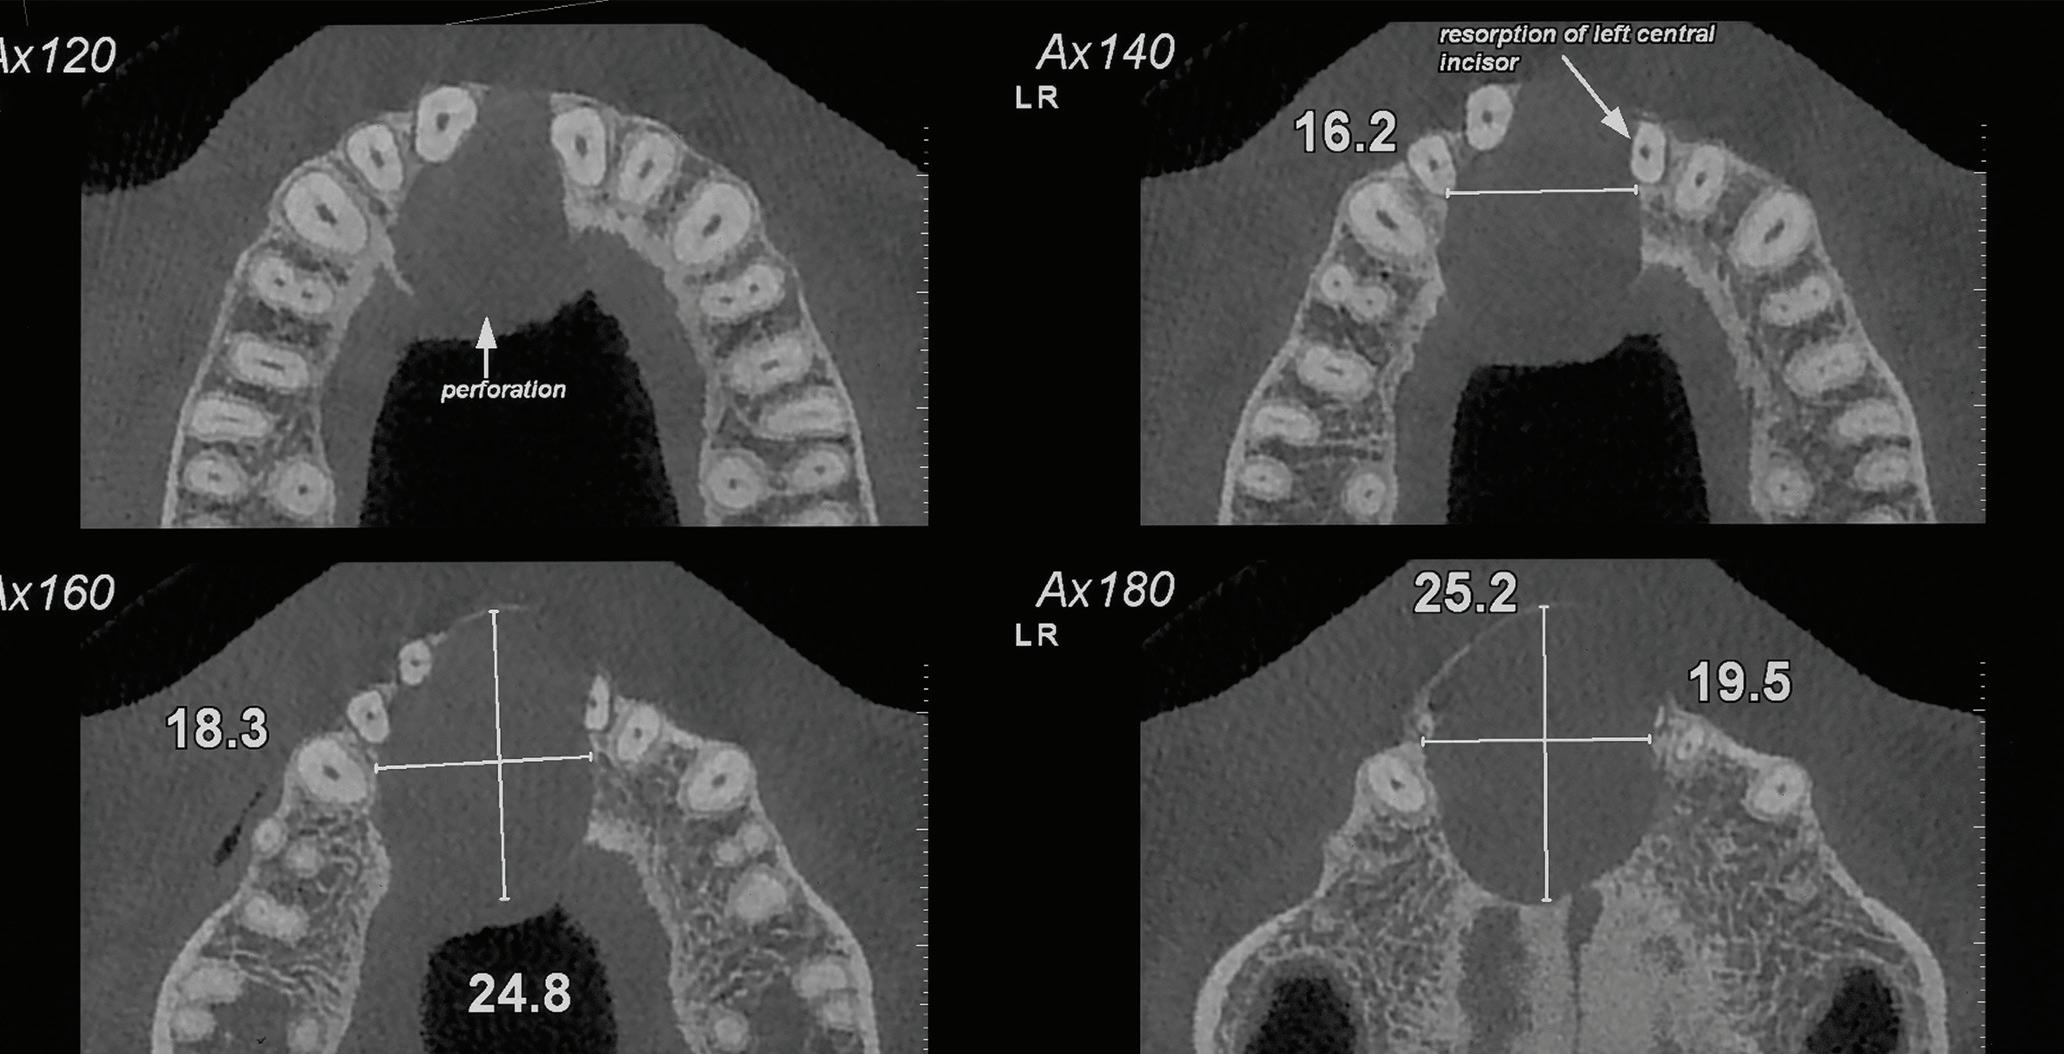

Root migration after coronectomy of impacted mandibular third molars: case reports

Gustavo Henrique de Souza Silva Enzo Balestrero

Jéssica Lemos Gulinelli

Pâmela Leticia dos Santos